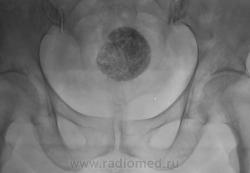

Пациентка направлена на рентгенографию тазобедренного сустава по поводу "артроза". Беспокоят вроде-бы боли в области правого тазобедренного сустава. Произведена рентгенография в прямой стандартной проекции. Рентгенологических данных за артроз не было. Но по краю пленки что-то "маячило". Пациентке 56 лет.

Досняли... Ваше мнение уважаемые коллеги?

Или конкремент мочевого пузыря или фиброматозный узел с обызвествлением. Если в больнице есть УЗИ.... нет - экскреторная, до нее можно латерограмму, пневмоцистограмму и т.п.

Добрый вечер, Валентин Львович! Представленный Вами случай - обызвествление миомы матки, раза три наблюдал. Неплохо бы боковую проекцию, вдруг хондрома крестца.

Вообще-то весьма характерная картина фибромиомы матки, осмотра гинеколога и УЗИ вполне достаточно

Согласен, и даже без каких-либо минимальных возражений

Случайная находка.Пациентка 49 лет пришла на снимок тазобедр. сустава. На  УЗИ изменения в матке.скорее всего обызвествления находятся именно там.